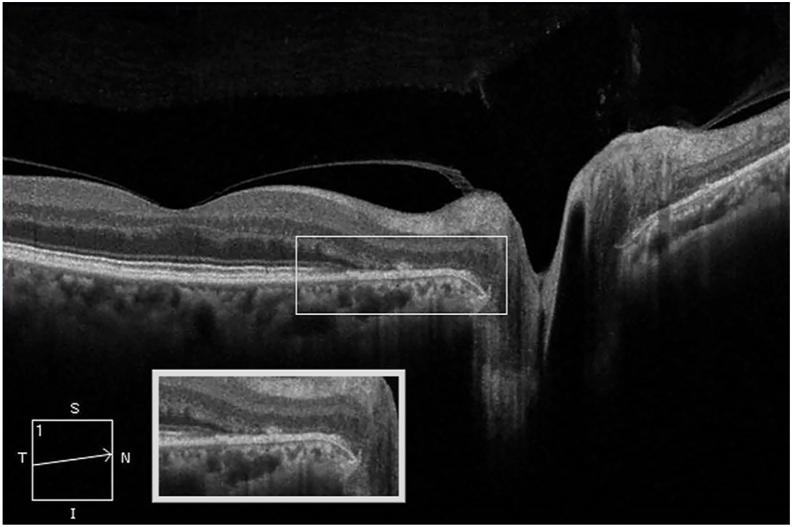

A 57-year old woman presented with a one-month history of photopsia, temporal visual field disturbance on the right eye, 11 days following the administration of the influenza virus vaccine. Visual acuity was 20/30, and color vision remained normal. Examination revealed mild venular dilation at the edge of the right optic disk and was otherwise unremarkable. Visual field testing revealed enlargement of the right physiological blind spot. Medical workup, including brain CT scan, brain MRI, RPR, antibodies, Chest X-Ray, ANA, and PPD testing, was found within normal limits. Ancillary testing was compatible with an assessment of AIBSES secondary to influenza virus vaccination.

一名57岁女性在接种流感病毒疫苗11天后出现为期1个月的闪光感及右眼颞侧视野障碍。视力为20/30,色觉正常。检查发现右眼视盘边缘轻度静脉扩张,其他未见明显异常。视野检查显示右眼生理盲点扩大。包括脑部CT扫描、脑部MRI、快速血浆反应素试验(RPR)、抗体、胸部X线、抗核抗体(ANA)及结核菌素试验(PPD)在内的医学检查均在正常范围内。辅助检查结果符合对流感病毒疫苗接种继发AIBSES的评估。